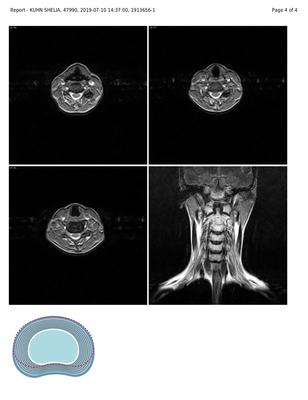

Over the last 20 years, I have lost the ability to extend my right thumb and forefinger. My wrist is very weak. I cannot even pick up a glass of water. I have had multiple MRI's of my shoulder and cervical spine. Nothing has been found. On the last MRI report they reported "Concurrent bilateral uncovertebral joint degenerative change is seen. Disc material and uncovertebral joint degenerative change cause mild left neural foraminal narrowing. Bilateral exiting nerve roots are normal. Disc deformity measures 2.3 mm in neutral 1.9 mm in flexion and 2.3 mm in extension position."

Unfortunately the images and reports are too small to read. Please look: is there any mention of cervical ribs?